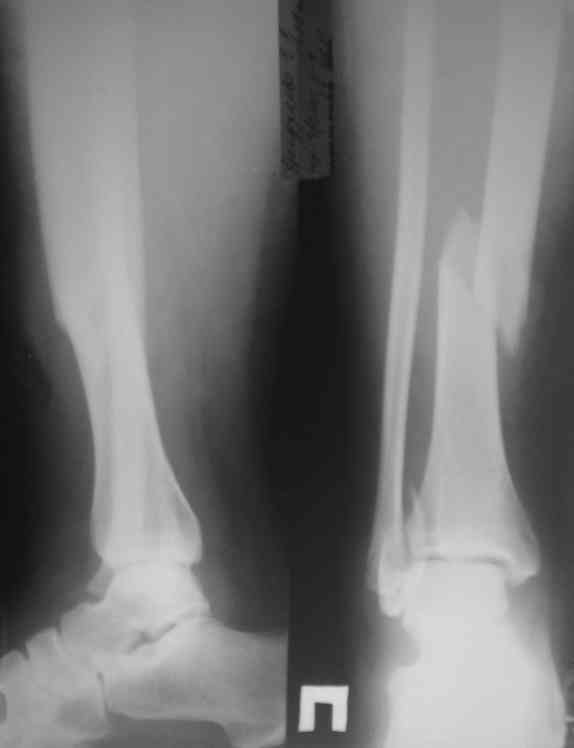

Механизм травмы - подвернул ногу. На боковом снимке видно, что латеральная лодыжка поломана на уровне голеностопного сустава. Во время травмы, кроме воздействия крутящего момента на кости голени, происходило еще и  стремительное движение тела больного вниз вместе с проксимальным отломком малоберцовой кости (сила земного притяжения), вследствие чего разрывается межкостная мембрана, передняя межберцовая связка (lig.tibiofibulare anterius), рудиментарная поперечная связка. На боковом снимке конец проксимального отломка ( в данном случае место прикрепления передней межберцовой связки) находится на уровне середины таранной кости. Соответсвенно, последняя разорвана. Смещение отломков костей голени по длине - около 2 см.

Соответственно, из составляющих ДМС осталась целой

лишь задняя межберцовая связка. Хирургу, который будет оперировать пациента, рекомендовано  наложить шов передней межберцовой связки, и ввести позиционный винт выше ДМС.